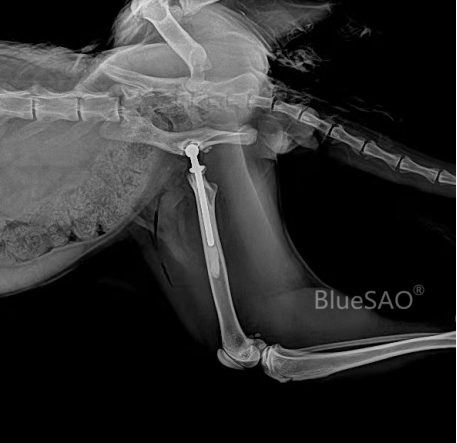

图 缅因猫进行骨水泥修复